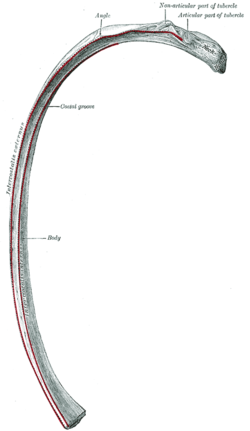

القفص الصدري جزء من الهيكل العظمي البشري يتكون الهيكل العظمى عند الانسان من الهيكل المحورى والهيكل الطرفى حيث نجد ان الهيكل المحورى يتكون من العمود الفقرى والقفص الصدرى والجمجمة . القفص الصدرى عند الانسان يتكون:

- 12 زوج من الضلوع التى ترتبط الجزء الخلفى منها بالعمود الفقرى.

- العشرة ازواج الاولى من الضلوع تتصل من الامام بعظمة القص

- الزوجان السفليان سائبان يسميان بالضلوع العائمة

Side view of human rib cage. Seen are the 5-12 spareribs under lean muscle.